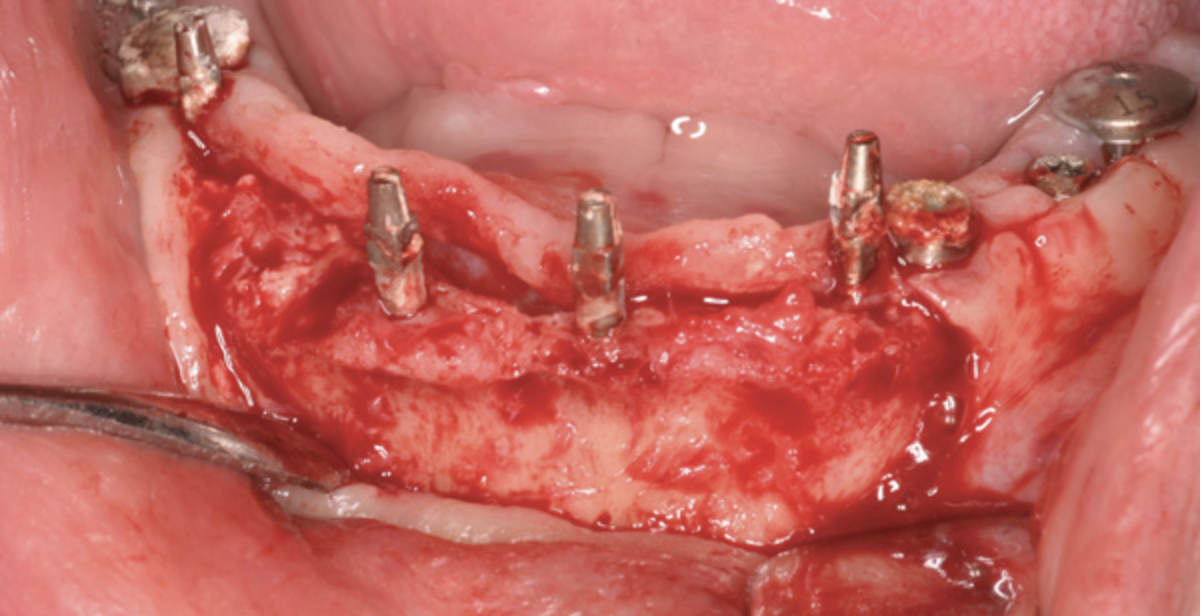

The patient shown in Figure 1 had presented after significant endodontic-related abscesses reduced the height of both buccal and lingual plates of bone. Covering the biphasic calcium sulfate (BPCS) graft with a dense polytetraflouroethylene (PTFE) barrier for 3 weeks enhanced healing in the site. Clinically, it is apparent that the ridge volume was maintained over 5 years and supported keratinized tissue (Figure 2). Most importantly, there was, on histologic evaluation, 58% vital bone, with no remnants of the bone replacement graft material (Figure 3).

Fig 1. A significant loss of bone necessitated covering the BPCS with a dense PTFE barrier.

Figure 1